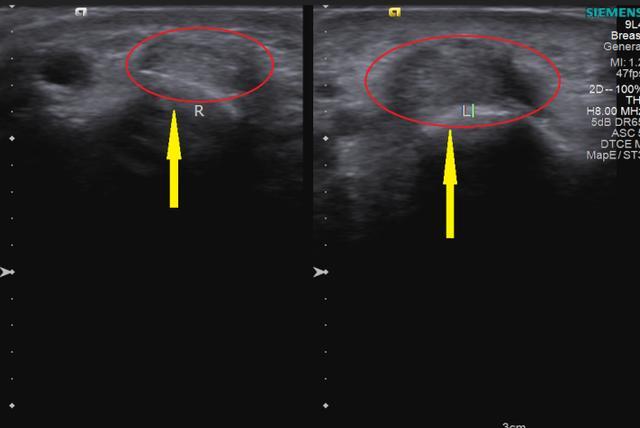

超声结果提示:左侧手腕拇长展肌腱、拇短伸肌腱腱鞘较对侧明显增厚。原来李阿姨是得了“妈妈手 ”。

超声结果显示:左侧手腕拇长展肌腱、拇短伸肌腱腱鞘较右侧明显增厚,回声减低。